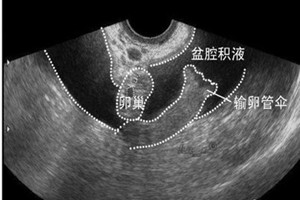

妇科医生表示:盆腔积液是女性重视度极高的疾病,因此对于盆腔积液女性要及早的发现早治疗。盆腔积液的患者在日常生活中要多加注意一些文体,以免病情恶化,增加治疗的难度。盆腔积液是女性常见的一种疾病,是导致女性不孕的重要原因。很多女性朋友得了盆腔积液之后感到紧张,不知所措。那么,女性得了盆腔积液怎么办?